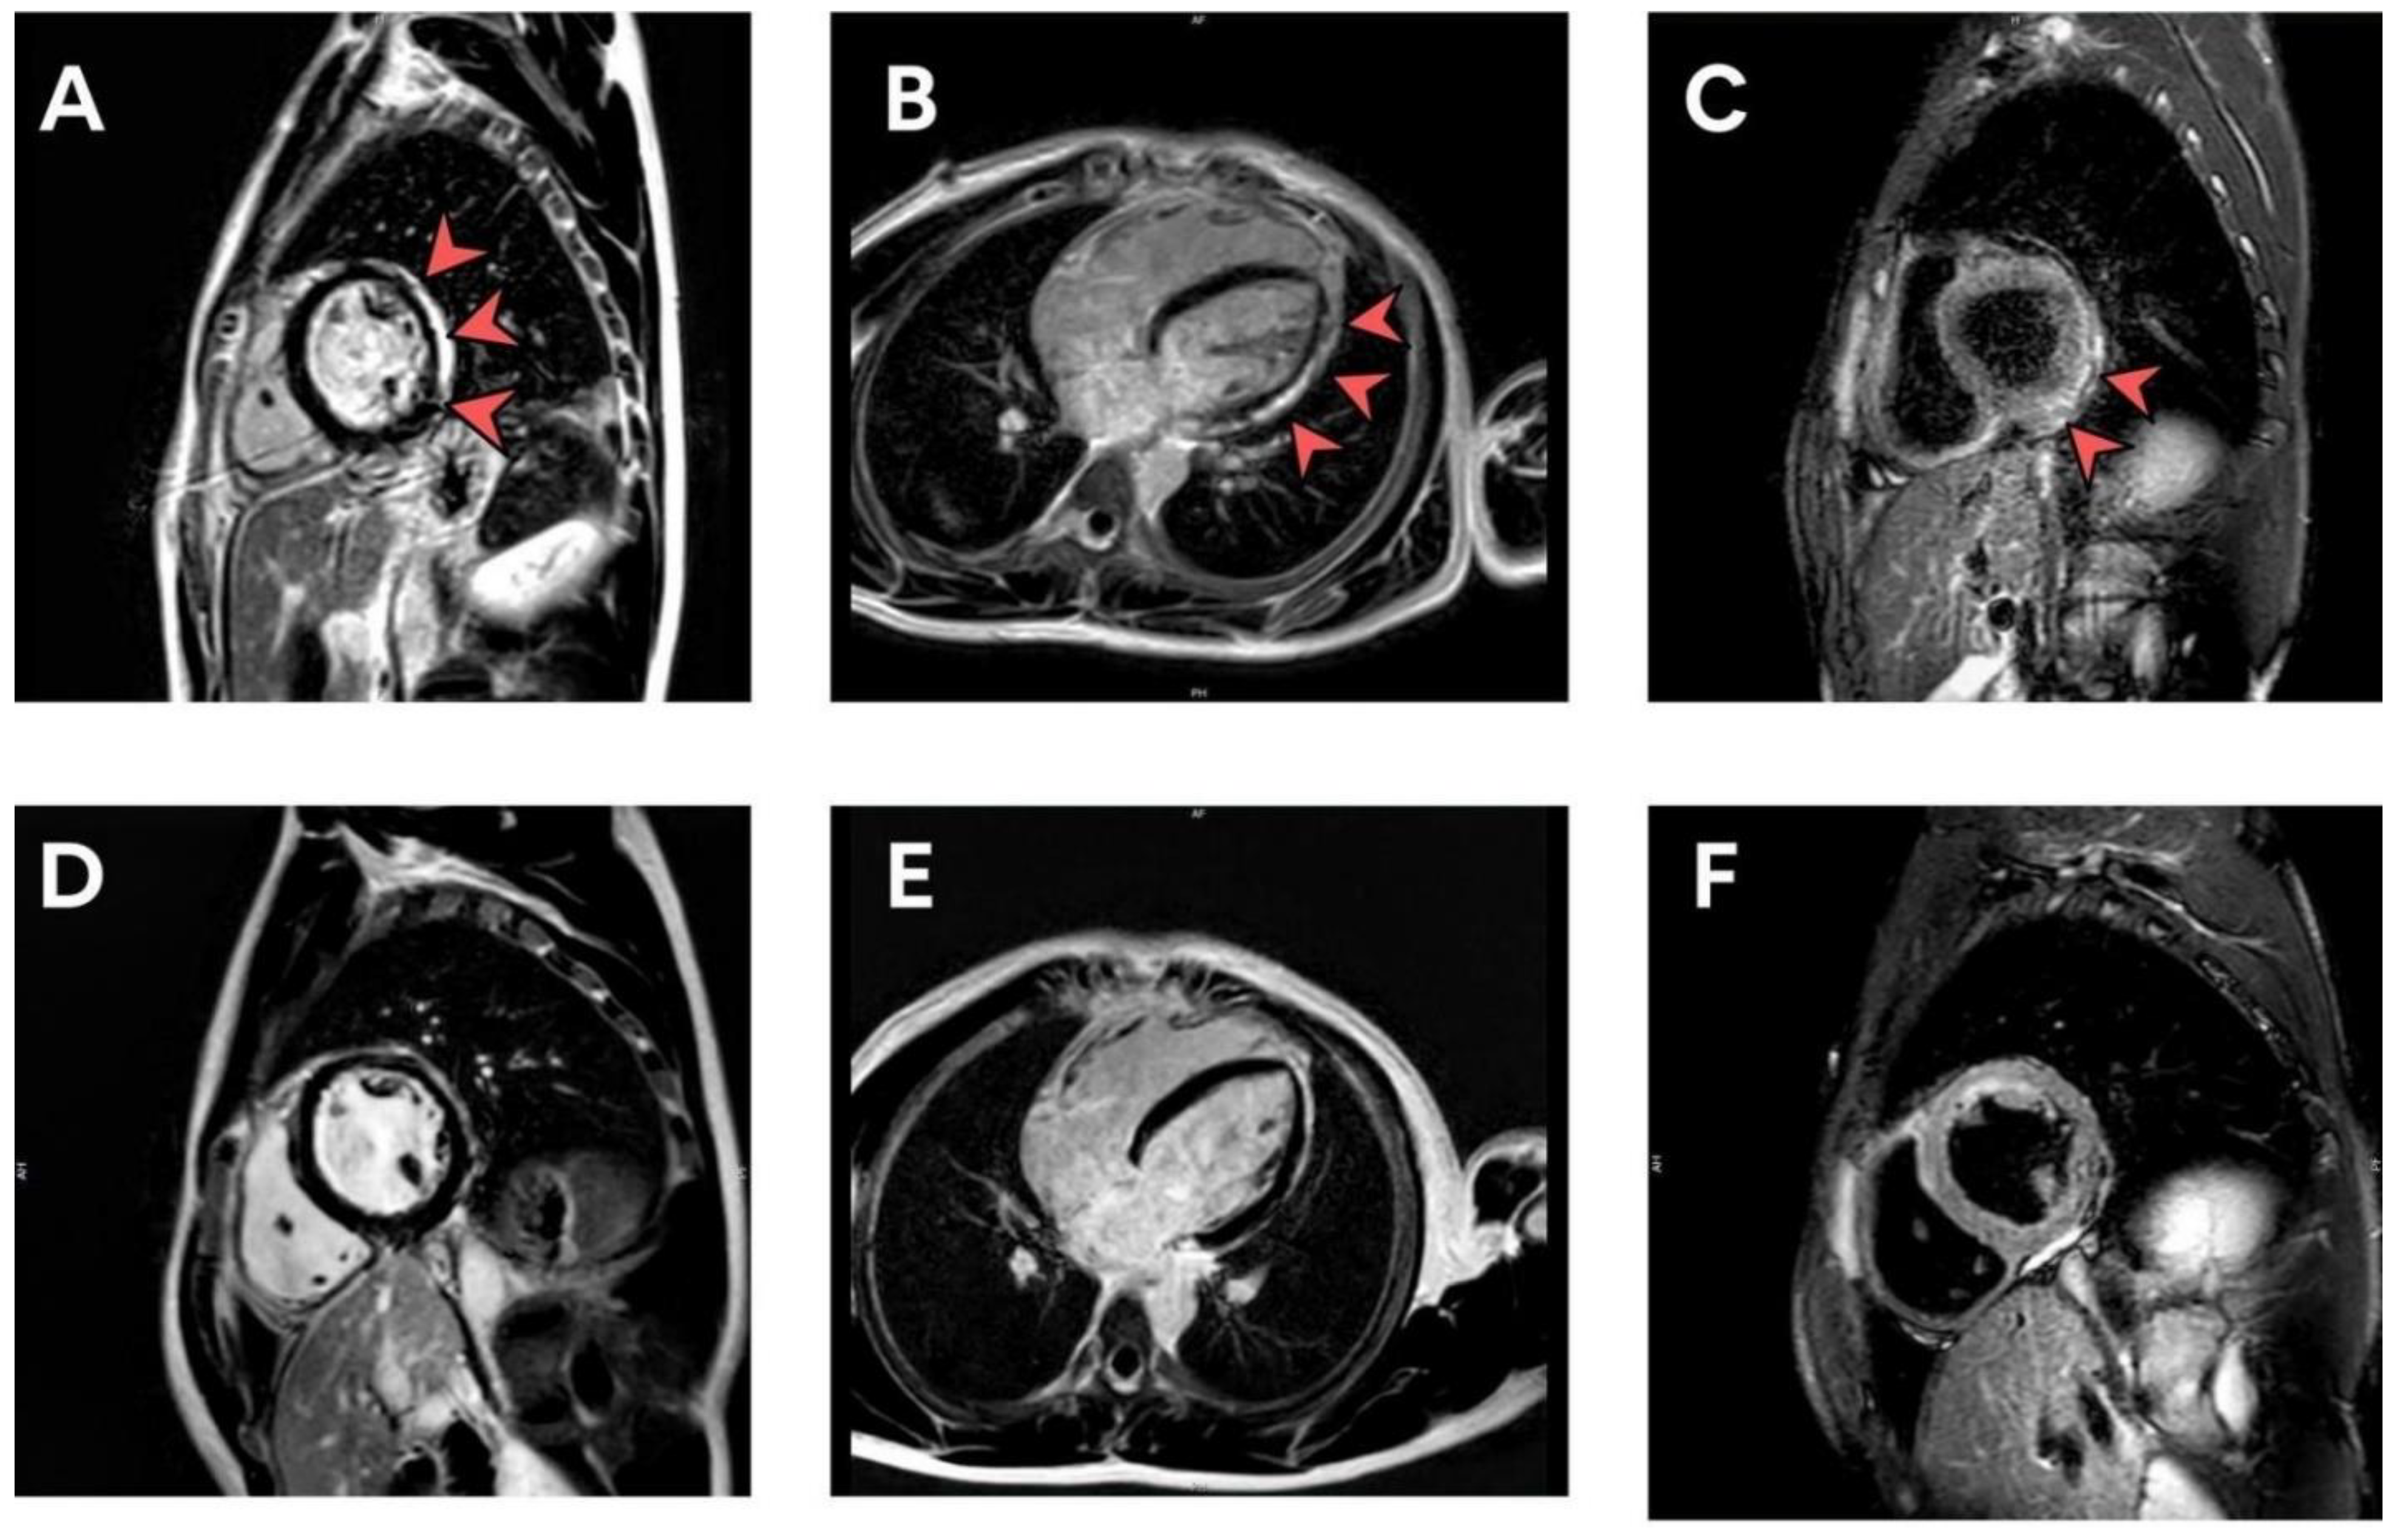

3.3. Evaluation of Patients with Elevated Biomarkers or Positive Lab Assessments

4. Discussion